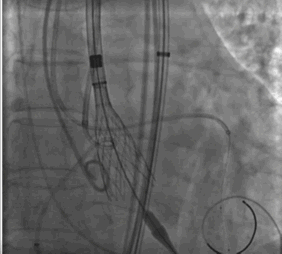

按照预先制定手术策略,首先,周玉杰教授内科团队首先进行左右冠脉保护,然后进行超硬导丝跨瓣进,23mm快速起搏预扩,左右冠脉均无显影,证实冠脉预先评估无误,选择右冠脉居中体位释放,利用瓣膜底部与无冠猪尾导管定位,快速起搏开始释放,释放至限位,由于是可回收系统进行多次反复观察评估冠脉情况,释放位置稳定较好,确认冠脉无风险完全释放瓣膜,撤出体外。

术后评估冠脉情况,瓣膜型号Downsize选择26mm恰好。无球囊后扩,主动脉瓣膜无反流,平均压差6.7mmHg。